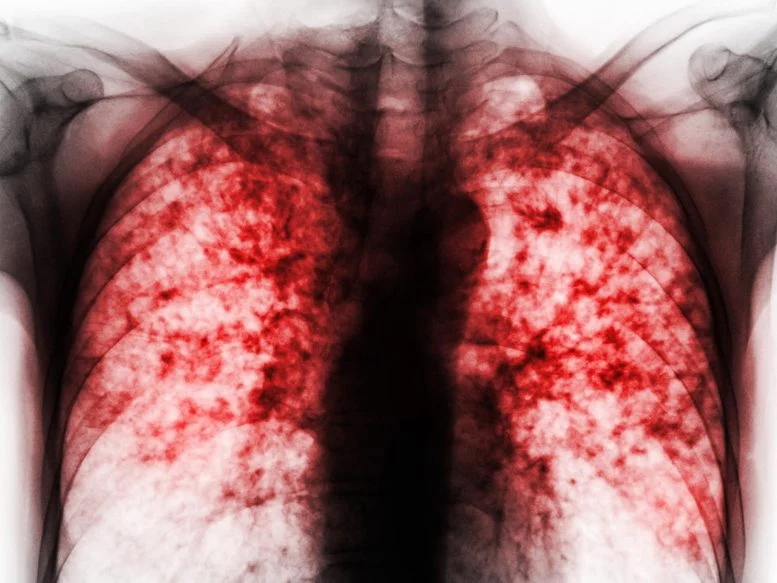

Penyakit menular paling mematikan di dunia ini sangat membutuhkan antibiotik baru dan efektif. Para peneliti telah menciptakan senyawa baru yang menjanjikan yang mungkin menandai langkah maju yang besar dalam upaya global untuk memerangi tuberkulosis, penyakit menular paling mematikan dalam sejarah manusia. Menurut sebuah studi baru yang diterbitkan di Nature, senyawa yang disebut CMX410, bekerja dengan menyerang (…)